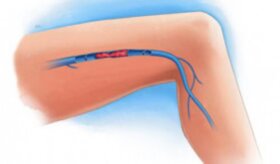

약을 먹지 않고 혈압을 낮추는 방법이 있을까? 고혈압은 치료하지 않으면 심장마비 같은 심혈관계 문제나 사망까지도 이를 수 있다. 따라서 고혈합은…